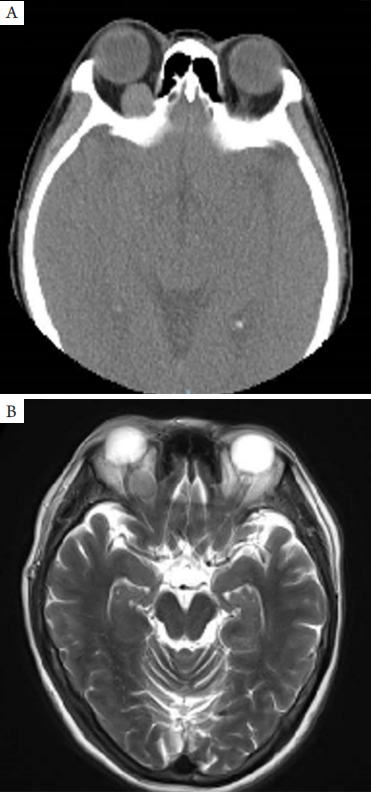

患者,女,53岁,因“右眼眼睑抬举无力2个月,发现右眼眼眶肿物1周”,于2018年2月2 7日收住河南省立眼科医院。就诊前2个月,患者无明显诱因出现右眼眼睑抬举无力,行头颅及眼眶核磁共振检查时发现右眼眼眶内肿物,考虑血管瘤可能,无疼痛、压痛,无眼痛、复视、视物模糊、流泪,无头痛、恶心、呕吐等不适,今来河南省立眼科医院就诊。既往2 5年前曾患甲状腺功能亢进,高血压病史2个月,血压控制良好,其他无异常。眼部检查:视力右眼1.2,左眼1.2;右眼眼睑无充血,无水肿,上睑不全性上睑下垂(图1);眼前节检查和眼底检查均未见明显异常;眼压13.1 mmHg(1 mmHg=0.133 kPa),眶压Tn,眼球运动自如。左眼检查未见明显异常。眼突度右眼18 mm,左眼16 mm,眶间距100 mm。眼眶C T示双侧眼球无突出,眼环对称无增厚,右眼球后方可见类圆形均匀密度影,边界清,大小约1.4 cm×1.5 cm×1.4 cm,邻近视神经、内直肌及上直肌受压,左眼球后及眼球内未见异常密度影及占位病变。提示右眼眶内占位性病变(图2A)。眼眶MRI示右侧眼眶内球后可见一类圆形等T1稍长T2异常信号影,大小约1.4 cm×1.4 cm×1.3 cm,其内信号均匀,边界清晰。病灶与眼球分界清,眼球受压向前稍突出,视神经受压向右侧偏移,右眼上、内直肌亦受压移位。经静脉注入钆喷酸葡胺(gadolinium diethylenetriamine pentaacetic acid,GD-DTPA)后扫描,该病灶呈明显尚均匀强化,左侧眼眶内未见明显异常,考虑右眼眶占位性病变,血管瘤可能(图2B)。临床诊断:右眼眶内肿瘤。

图2 眼眶CT和MRI检查结果

Figure 2 Orbital CT and MRI images

(A)眼眶CT示右眼球后方可见类圆形均匀密度影,边界清;(B)眼眶MRI示右侧眼眶内球后可见一类圆形异常信号影,其内信号均匀,边界清晰,内直肌和视神经受压。

(A) Orbital CT shows that the tumor is quasi-circular with homogenous density and clear boundaries; (B) Orbital MRI shows that the tumor is quasi-circular, well-circumscribed and with homogenous intensity. Note the medial rectus and optic nerve is compressed.

眼眶副神经节瘤多位于球后肌锥内、眶尖附近或靠颞侧[2]。临床表现为眶内占位引起的症状,无特异性,难以确诊。本例患者出现上睑下垂,推测原因可能是由于提上睑肌在上直肌上方向前走行受到肿瘤压迫或肿瘤同时压迫动眼神经上支所致。副神经节瘤影像学特点为富血供软组织结节,有完整包膜,CT及MRI增强扫描瘤体强化明显[5-7],但因该肿瘤临床表现多变,单纯根据影像学表现,难以做出正确诊断。本例患者行眼眶MRI检查时增强扫描瘤体强化明显,亦考虑为血管瘤可能。